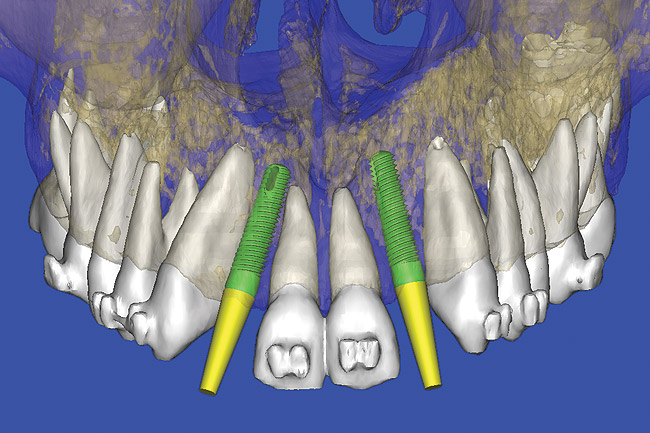

Using the interactive treatment-planning software application, the scan data was assimilated and both potential lateral incisor implant receptor sites were evaluated. It is a combination of the data and the methodology used to interpret the data that is the basis for defining a new paradigm in diagnosis and treatment planning. Proper evaluation of these images and correct use of the interactive treatment planning software tools is essential in creating a decision tree of treatment options. First, the data from the scan was reformatted into panoramic, axial, and cross-sectional images. The undistorted cross-sectional images revealed the residual alveolar bone in the area of the right lateral incisor. Then, a simulated schematic implant was placed within the bone with an abutment extension to help visualize the connection to the restorative position of the tooth (Figure 6). The Triangle of Bone® (TOB), a concept developed by the author to analyze bone quality, quantity, and disposition at prospective dental implant sites using CBCT scans, aided in determining available bone volume by defining a “zone” for proper implant placement18,19 (Figure 7).

After reviewing the CT data and the decision tree, the bone within the “zone” of the TOB was evaluated and found to be satisfactory for implant placement. Because the goal of implant dentistry is not the implant but the tooth that is placed, true restorative-driven implant dentistry must begin with the assumption that the implant position should remain consistent with the tooth it is replacing, and the final implant-supported restoration.12,22-26 The TOB aids the clinician in understanding the link between the implant position and the desired restorative goal. The base of the geometric shaped “zone” is visualized by starting at the widest area of alveolar bone facially and superiorly. The apex of the triangle is positioned to bisect the alveolar crest (Figure 7). The TOB, the overlay in the cross-sectional image, reveals whether adequate bone is available for implant placement. It also helps to identify concave facial bone defects, and accurately determine the width of bone at the crest. The author recommends using an interactive software application that provides the necessary measurement tools to accurately assess the bone anatomy.

Figure 7  SOFTWARE IMAGING The determination of the "zone" for proper placement.

Figure 7